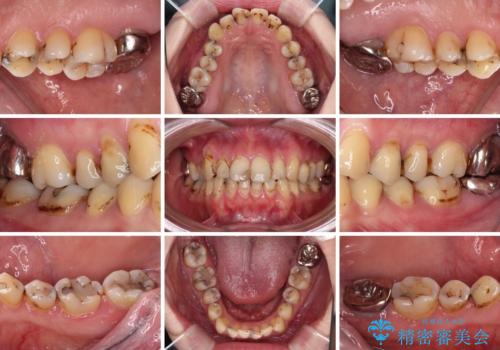

- 上下前歯や奥歯の虫歯治療を希望して来院された患者様です。

全顎的にむし歯が多く、根管治療の必要奥歯や、審美的に気になっている前歯を中心にオールセラミッククラウンにて補綴治療を行うこととしました。

上顎前歯は歯肉退縮により歯根が露出していたため、事前に歯肉移植術により根面被覆を行い、その後にオールセラミッククラウンを装着することとしました。